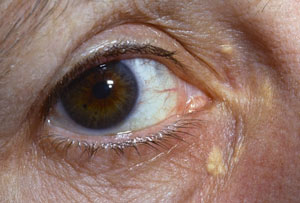

Медицинские исследования: эластическая псевдоксантома